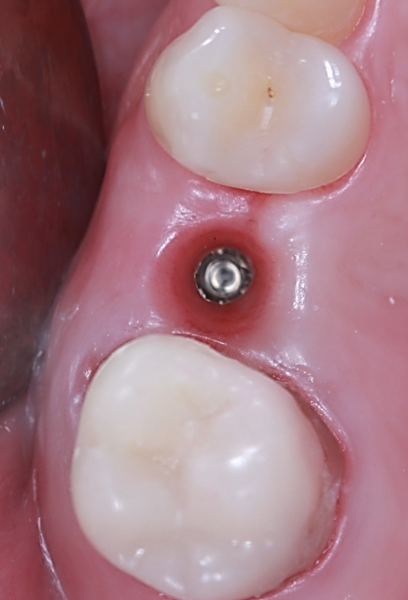

To preserve the ridge contour over time, cerabone plus was hydrated according to the manufacturer’s instructions and placed into the buccal gap at site #25 (Figs. 10a–f). Both sites received healing abutments and were sutured using mesial and distal single interrupted sutures to ensure soft-tissue stability during the healing phase (Figs. 11a–f & Figs. 12a–d). The patient received postoperative instructions along with an analgesic prescription and was scheduled for suture removal after two weeks.